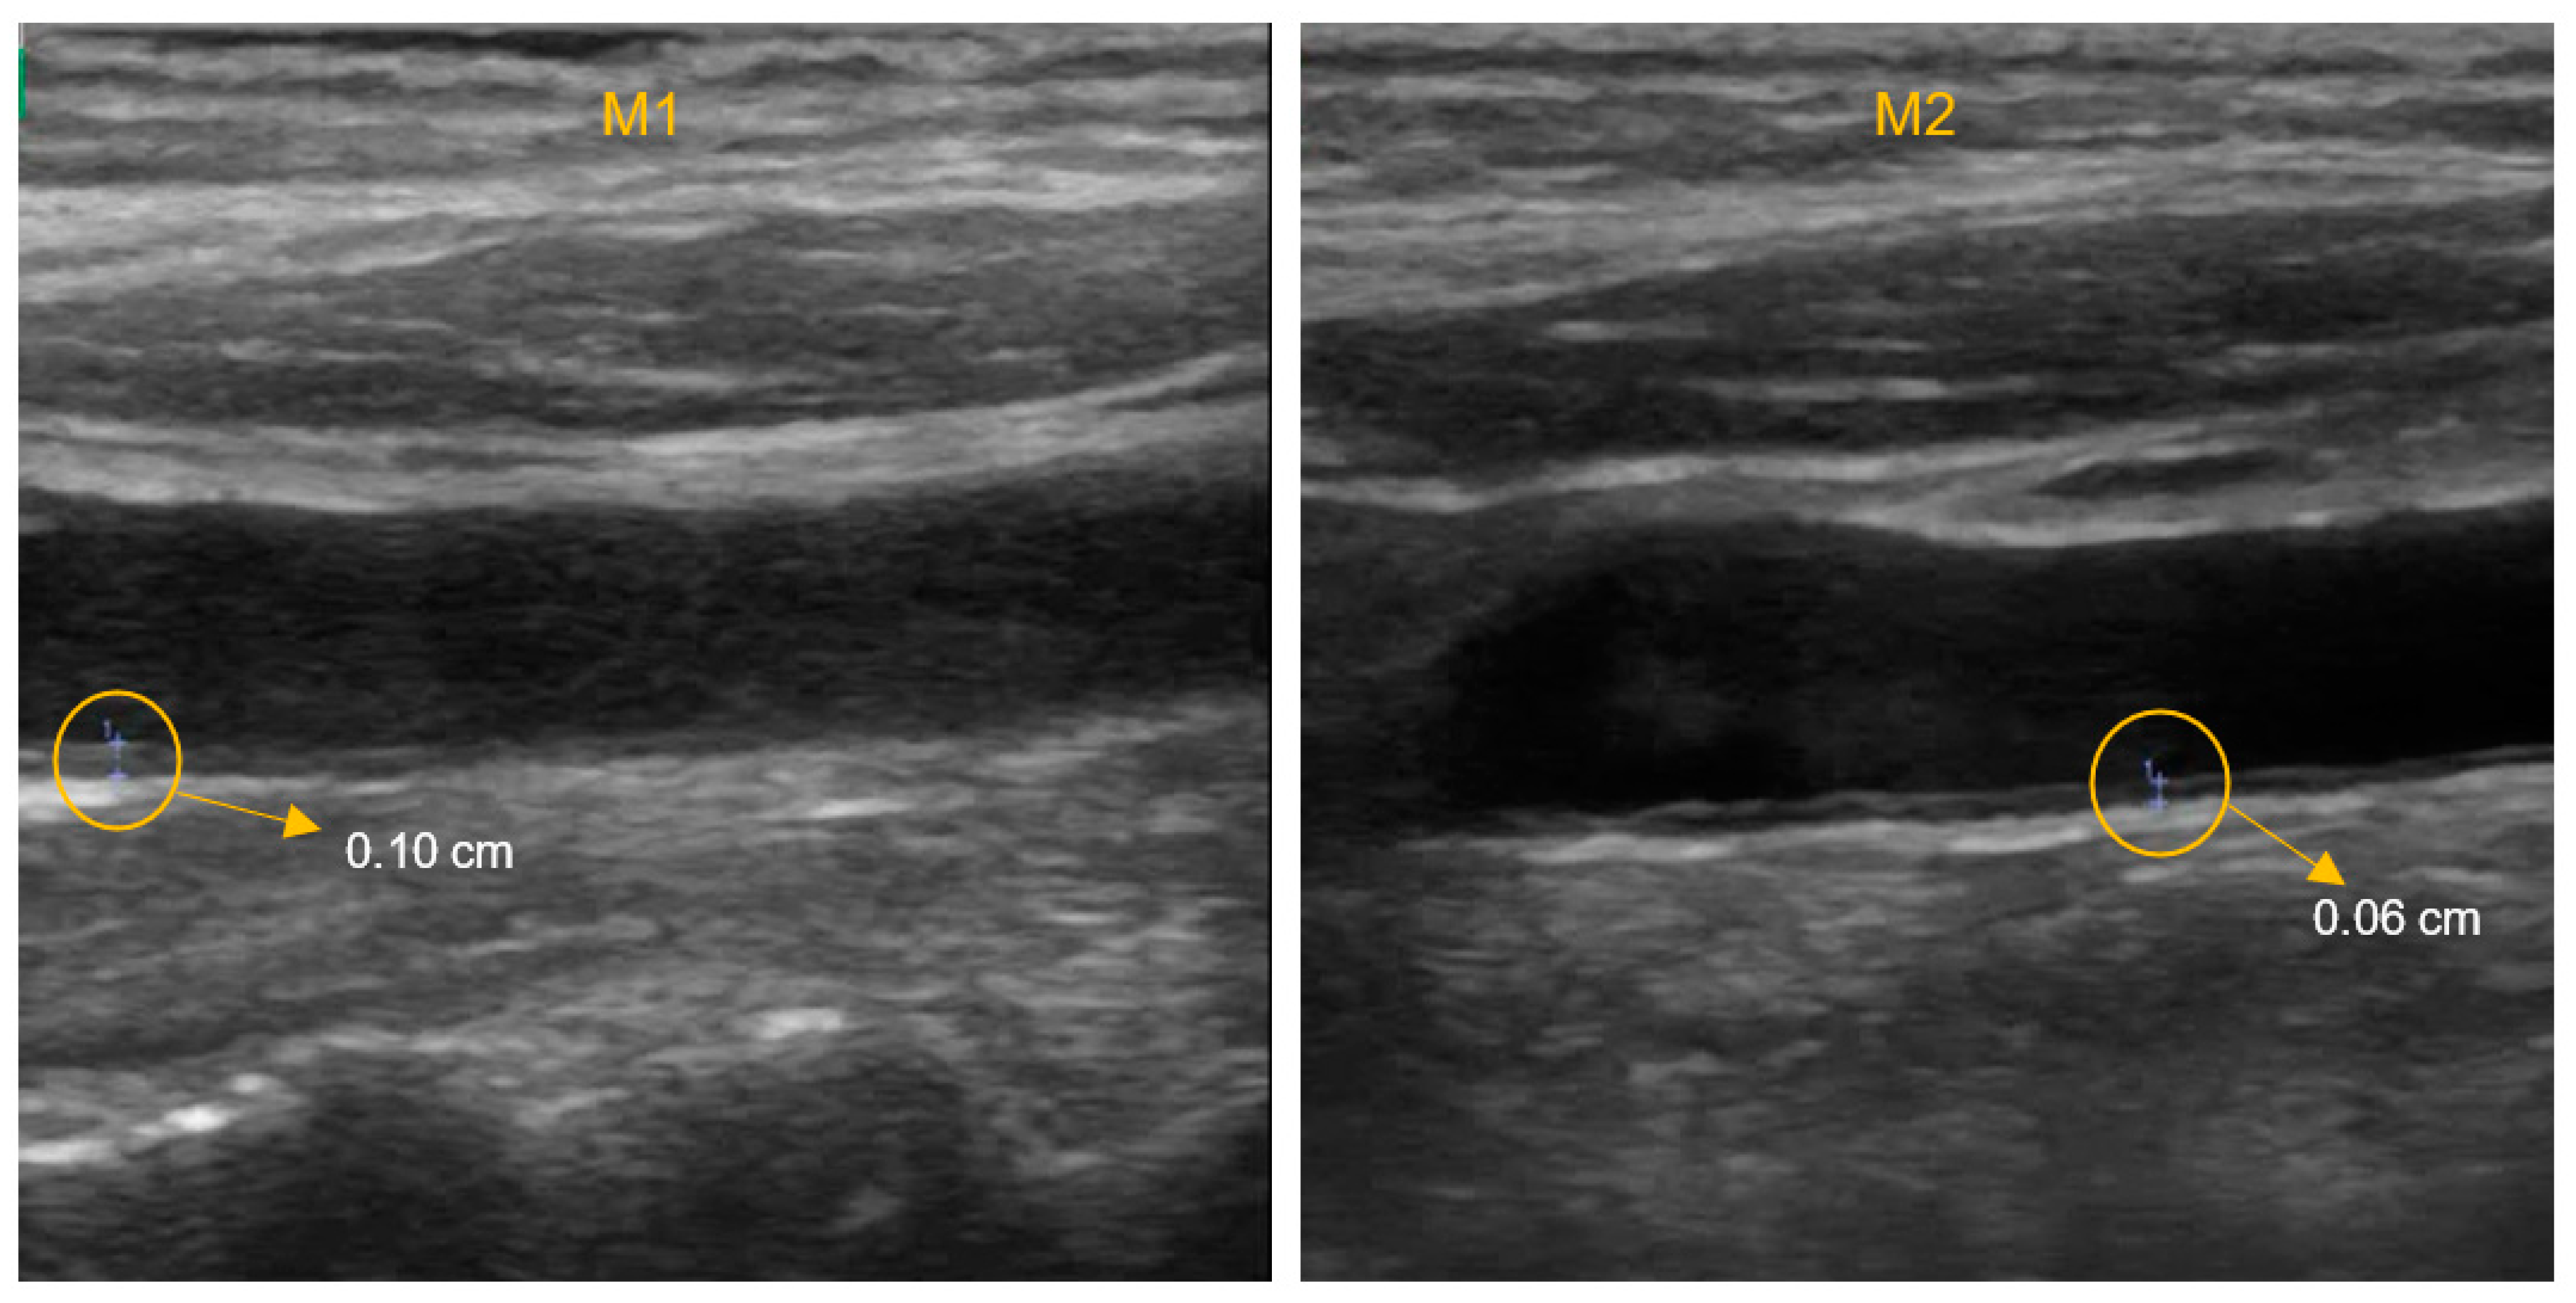

| IMT-L (cm) | 0.07 (0.02) | 0.07 (0.02) | 0.293 | 0.08 (0.02) | 0.07 (0.02) | 0.376 | 0.07 (0.02) | 0.07 (0.02) | 0.707 | 0.07 (0.01) | 0.07 (0.02) | 0.979 | 0.989 | 0.501 |

| IMT-R (cm) | 0.08 (0.01) | 0.07 (0.01) | 0.808 | 0.08 (0.02) | 0.07 (0.02) | 0.055 | 0.08 (0.02) | 0.07 (0.01) | 0.205 | 0.08 (0.02) | 0.08 (0.02) | 0.308 | 0.654 | 0.698 |